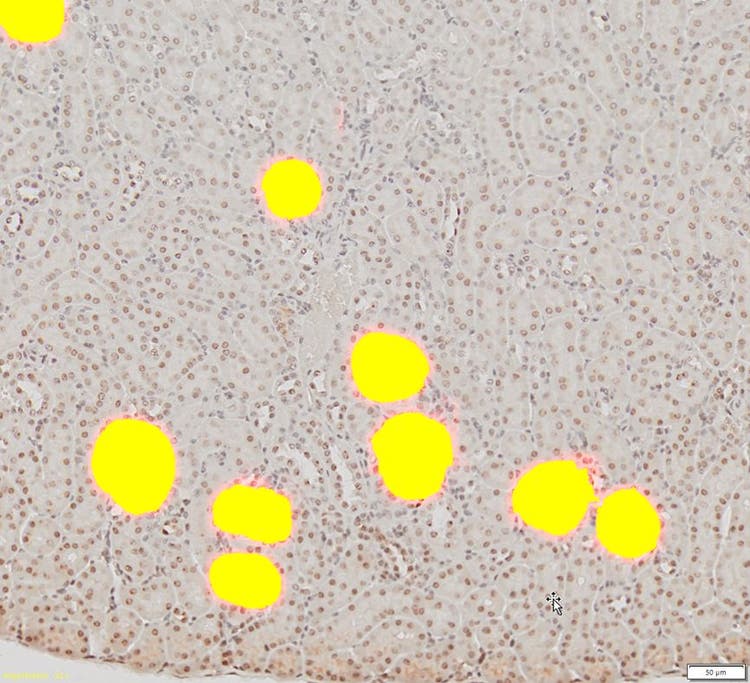

La DNN calculada se aplica al resto de las imágenes renales para detectar y separar automáticamente los glomérulos.

Por último, la DNN calculada se aplica al resto de imágenes renales para detectar y separar automáticamente los glomérulos.

3. Los glomérulos detectados pueden ser segmentados y utilizados para análisis posteriores de recuento y medición en la imagen generada.

Glomérulos detectados

El módulo TruAI™ permitió una fácil detección de objetos y segmentación de glomérulos a partir de imágenes complejas, con una fiabilidad y precisión mucho mayor que otros métodos automáticos existentes. Asimismo, es posible llevar a cabo otros análisis, como el recuento y la medición, en función de los resultados de la segmentación.